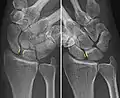

Shown is the right hand, palm down (left) and palm up (right). A=Scaphoid, B=Lunate

The scapholunate ligament is an intraarticular ligament binding the scaphoid and lunate bones of the wrist together. It is divided into three areas, dorsal, proximal and palmar, with the dorsal segment being the strongest part.[3] It is the main stabilizer of the scaphoid. In contrast to the scapholunate ligament, the lunotriquetral ligament is more prominent on the palmar side.